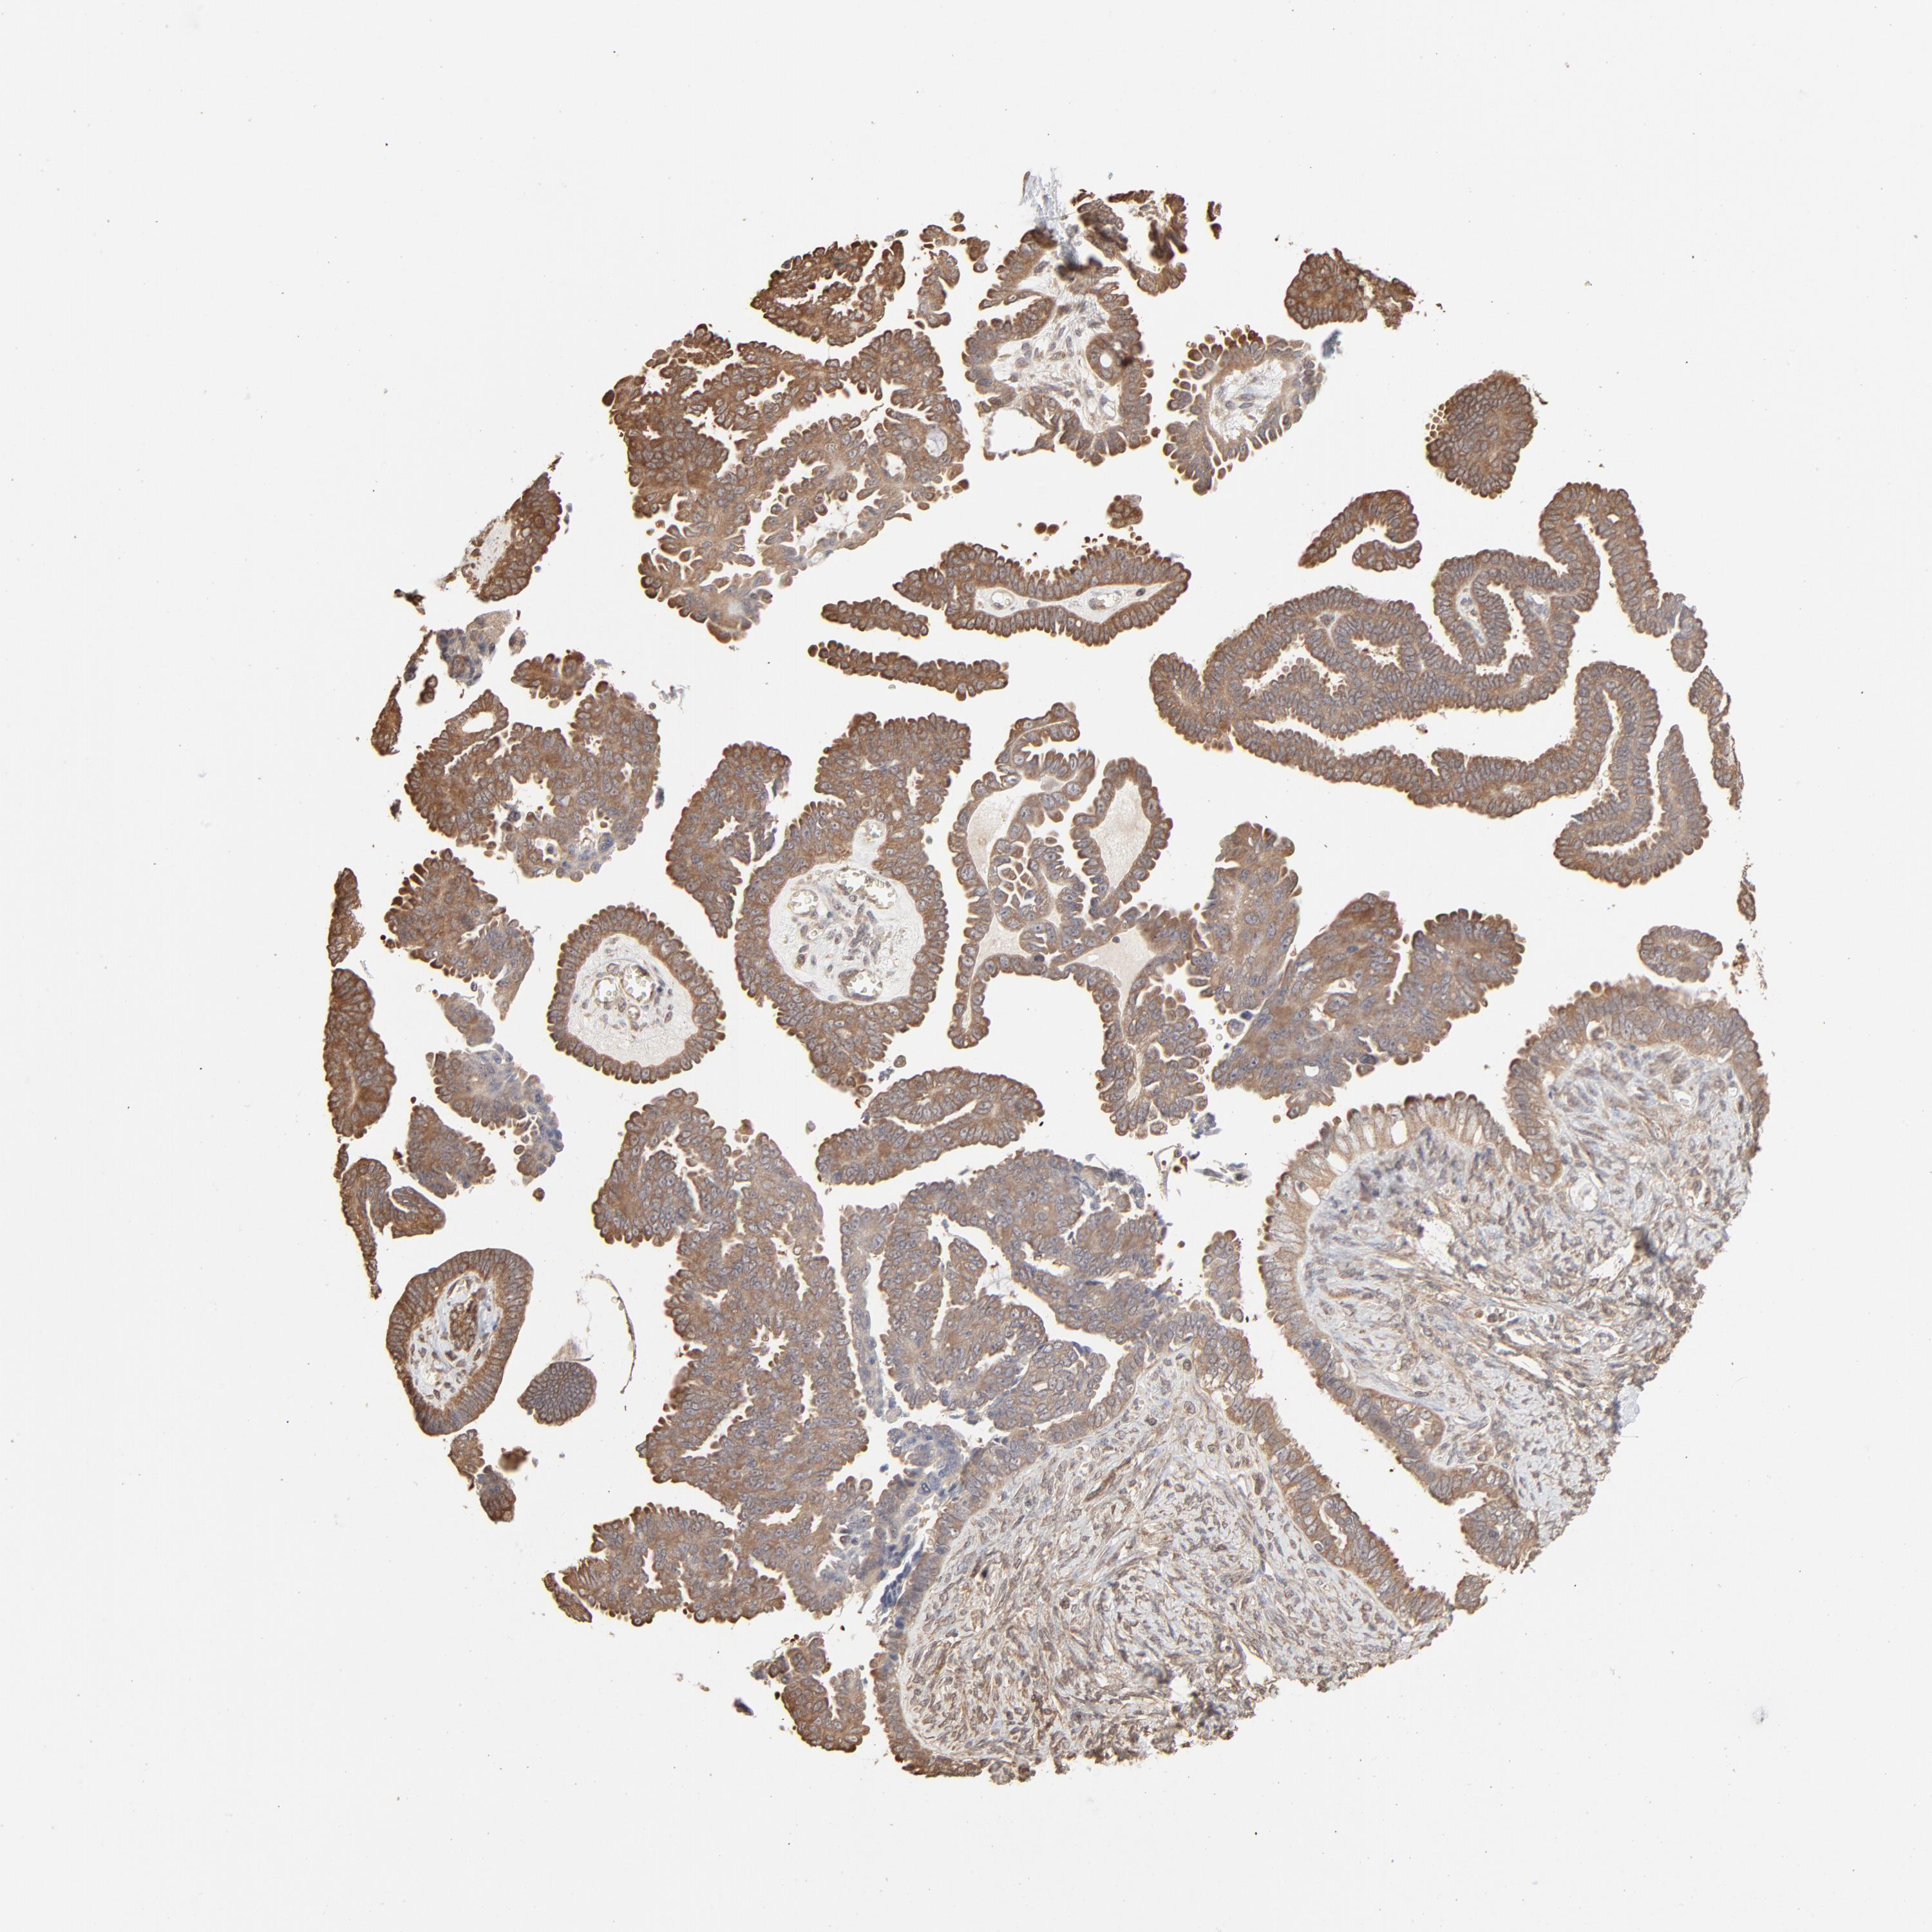

OVARIAN CANCER - Protein expressioni

A mouse-over function shows sample information and annotation data. Click on an image to view it in a full screen mode. Samples can be filtered based on level of antibody staining by selecting one or several of the following categories: high, medium, low and not detected. The assay and annotation is described here.

Note that samples used for immunohistochemistry by the Human Protein Atlas do not correspond to samples in the TCGA dataset.

Antibody stainingi

Antibody staining in the annotated cell types in the current human tissue is reported as not detected, low, medium, or high, based on conventional immunohistochemistry profiling in selected tissues. This score is based on the combination of the staining intensity and fraction of stained cells.

Each image is clickable and will lead to virtual microscopy that enables deeper exploration of all samples and also displays staining intensity scores, fraction scores and subcellular localization as well as patient and tissue information for each sample.

Antibody HPA043236

Antibody CAB003848

Cystadenocarcinoma, serous, NOS

Carcinoma, endometroid

Cystadenocarcinoma, mucinous, NOS

Carcinoma, NOS